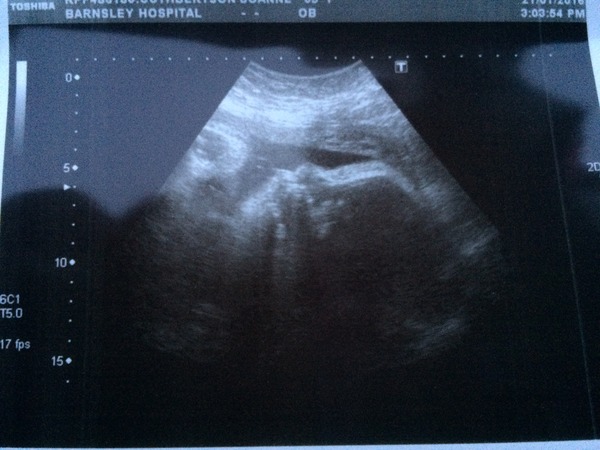

Phoenix80 · 21/01/2016 16:32

Today's scan pic. To say how many scans I've had this is one of the better photos because usually he doesn't co operate with scans 😀. The sonographer also said he has a lot of hair. Technology is amazing. My other boys' were born with lots of hair so it's not surprising 👶🏻💙

phoenix I love that they could see your baby's hair!!! My scans have come out with completely different measurements with only 24hrs between. It is so subjective where they take the points from. I've gone from measuring 1 week behind to 1 week ahead. Something interesting that I've been told at scans is that when baby is practising its breathing it isn't ready to come out. When it stops it is used as a warning that labour may be imminent.